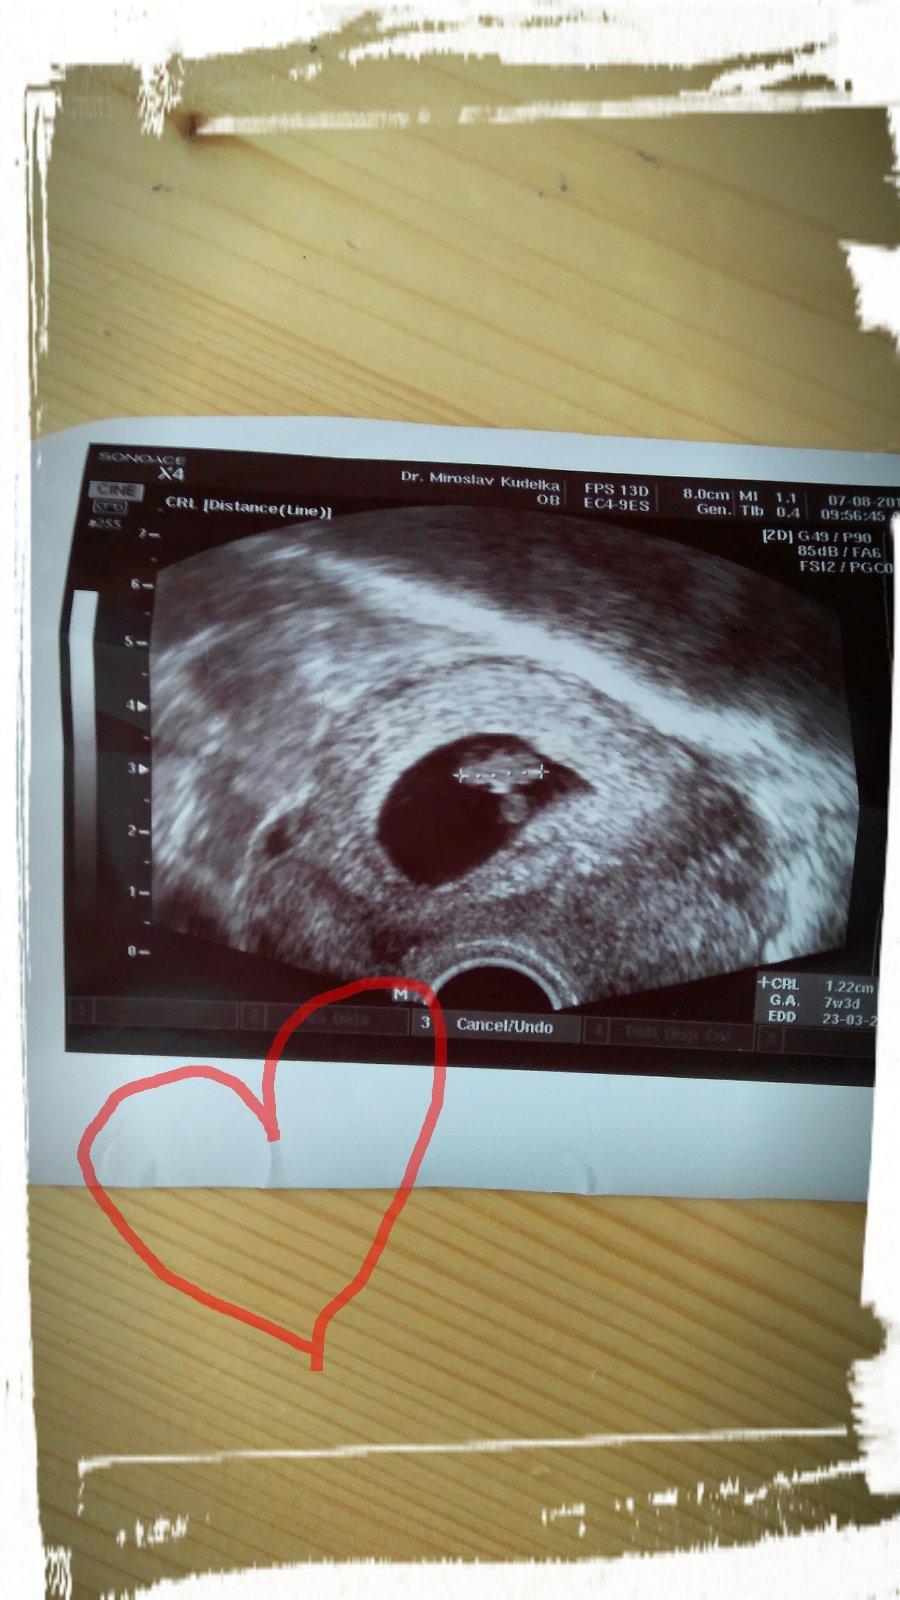

@vendelinka08 ahoj,tak já dnes byla u doktora a vše je v pořádku jsem šťastná 👍😉😊🤗.Srdíčko bije.Stari plodu odpovídá 7+3 a podle MS mam být 8+0.Tak teda nechápu,kdy došlo k oplodnění.Urcite ne během ovulka tu jsem měla kolem 16-17DC.

@cpollik to je uzasne..moc gratuluji a to cekani za to stalo!!!! Je tam vse co ma byt!!!

@vendelinka08 ale byly to nervy.Strasne jsem se bála.Ja stále nechápu,že mimco je 7+3 a podle MS jen o 4dny,takže jsem otěhotněla 4dny po MS? Každopádně jsem šťastná,že je vše v pořádku mimoděk nás.Asi by jsme měli založit novou diskuzi ať tu nenervujeme snažilky.